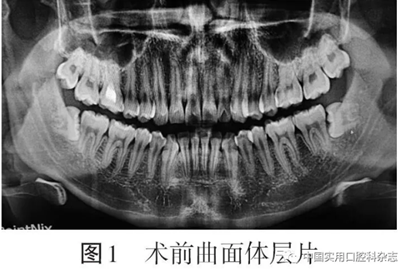

患者男,24歲,以“雙側下頜智齒拔除術后2 d伴胸痛”為主訴于2019-12-25來北京大學口腔醫院口腔頜面外科就診?;颊咦允? d前拍攝曲面體層片發現雙側下頜第三磨牙阻生(圖1)